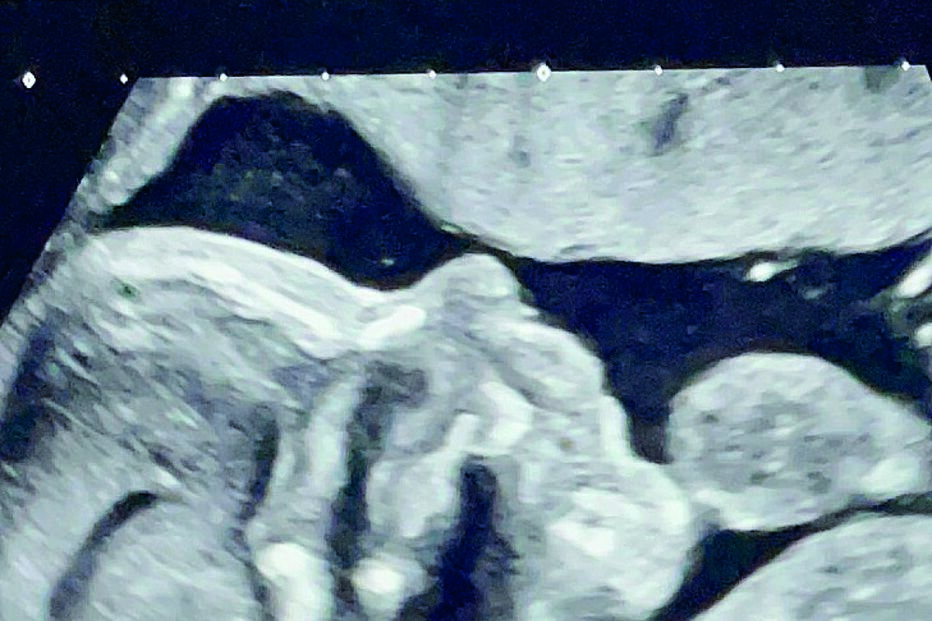

As nossas vidas seguem agora com uma companhia especial. O cargo que durará a nossa vida inteira, a de sermos pais.” Foi desta forma que Miguel Oliveira e Andreia Pimenta anunciaram que vão ser pais pela primeira vez. Nas redes sociais, o piloto de MotoGP, de 26 anos, partilhou a primeira fotografia em que é visível a barriga já saliente da companheira, que já passou o primeiro trimestre da gestação.

Além do anúncio da gravidez, o casal revelou ainda que aguarda com emoção a chegada de uma menina. “Ansioso por te conhecer filhota”, escreveu o piloto na legenda da publicação nas redes sociais. A notícia da gravidez surge três semanas após o casal ter trocado alianças numa cerimónia intimista. “Este fim de semana, realizámos a curva mais importante da nossa vida”, partilhou na altura Miguel Oliveira. Recorde-se que os dois mantêm uma relação desde a adolescência. O namoro começou aos 15 anos, em segredo, e só foi tornado público aos 19, porque Andreia é filha da madrasta de Miguel. O casal tentou esconder ao máximo a paixão porque viviam como irmãos, mas o amor superou todas as barreiras.

O casal optou por manter a gravidez em segredo durante vários meses. Até no casamento, que decorreu na última semana de julho, Miguel e Andreia optaram por esconder a chegada do primeiro filho. O vestido de noiva de Andreia tornou impercetível o crescimento da barriga.